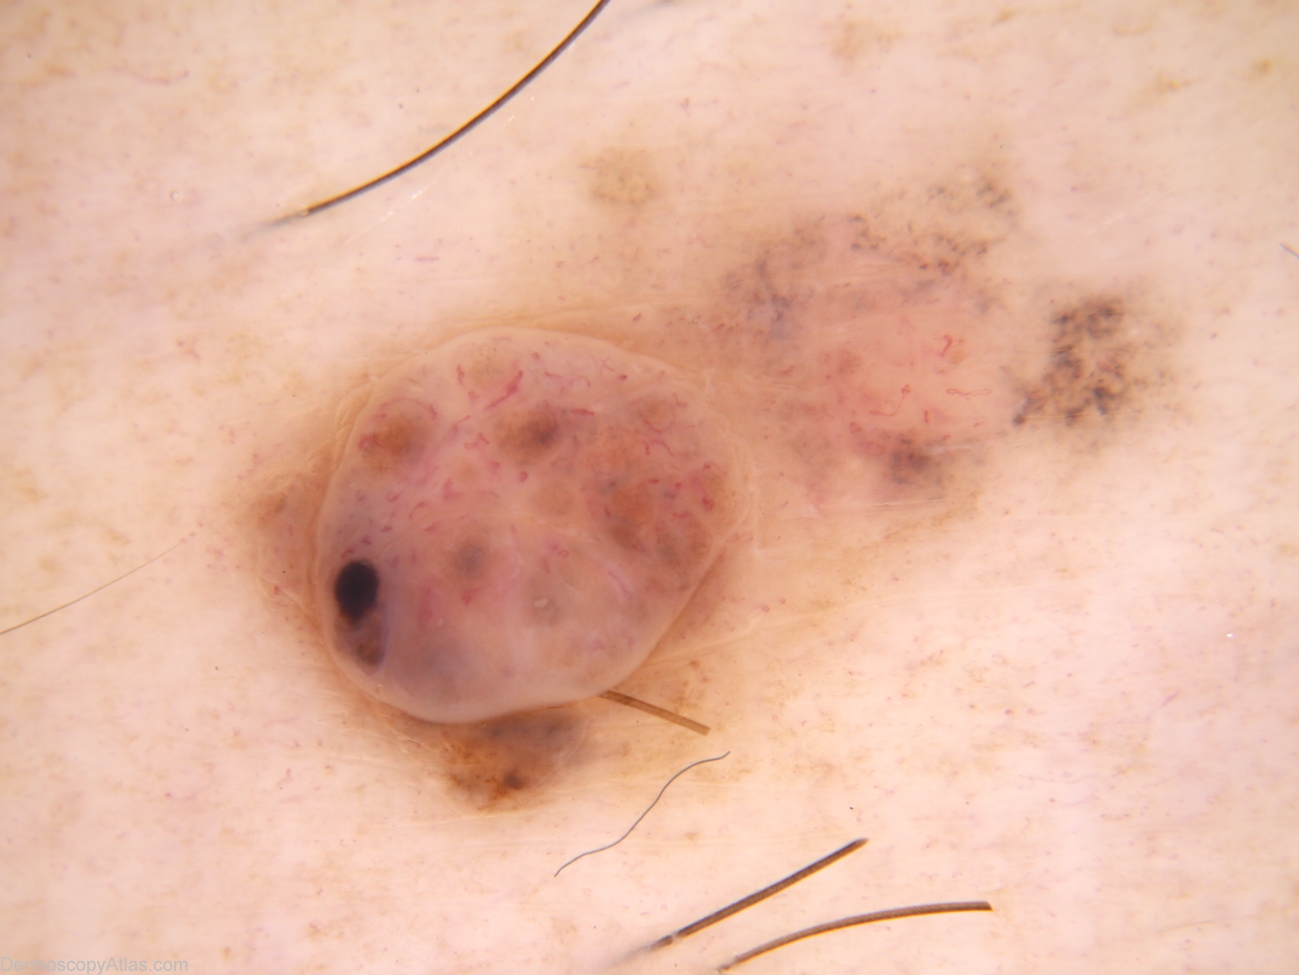

Description: The nodular component is not unlike a benign dermal naevus with maybe (in retrospect) more variability in vessel morphology and the unusual solitary brown clod. The macular component shows dots grey and more unusual fine hairpin vessels. Thes features suggest a (symptomatic) regressing melanocytic lesion.

History: 35 year old male with atypical mole syndrome. This lesion noted at examination prompted by melanoma 393. On asking, the patient mentioned this lesion had been irritated by clothing when active for the last 6-9 months. Histology reported as: Sections show a level 3 (0.8mm thick) nodular melanoma with prominent old regression. There is no ulceration, dermal mitoses or lymphocytic infiltrate.